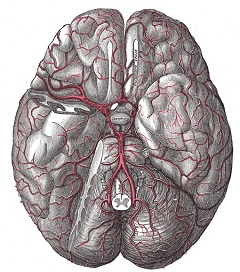

Виллизиев круг (circulus arteriosus cerebri Willisii) - это анастомоз между вертебрально-базилярной и каротидной системой кровоснабжения головного мозга. Он находится в основании головного мозга и представляет собой сеть артерий, имеющую форму овала с наименьшим поперечным диаметром. Свое название это анатомическое образование получило по фамилии английского врача, впервые описавшего его.

Виллизиев круг соединяет каждую из сонных артерий не только между собой, но и с системой позвоночных артерий. При нормальном развитии Виллизиева круга его правая и левая половины имеют симметричное строение.

Главной функцией Виллизиева круга является обеспечение полноценного кровоснабжения отдельных участков мозга, в случае вызванного какой-либо причиной нарушения кровотока в одной из шейных артерий.

Нормальное развитие Виллизиева круга встречается не более чем у 50% людей. Наиболее часто встречающейся патологией этой артериальной системы являются различные виды гипоплазий соединительных артерий. Аневризмы артерий головного мозга также чаще всего поражают сосуды Виллизиева круга.